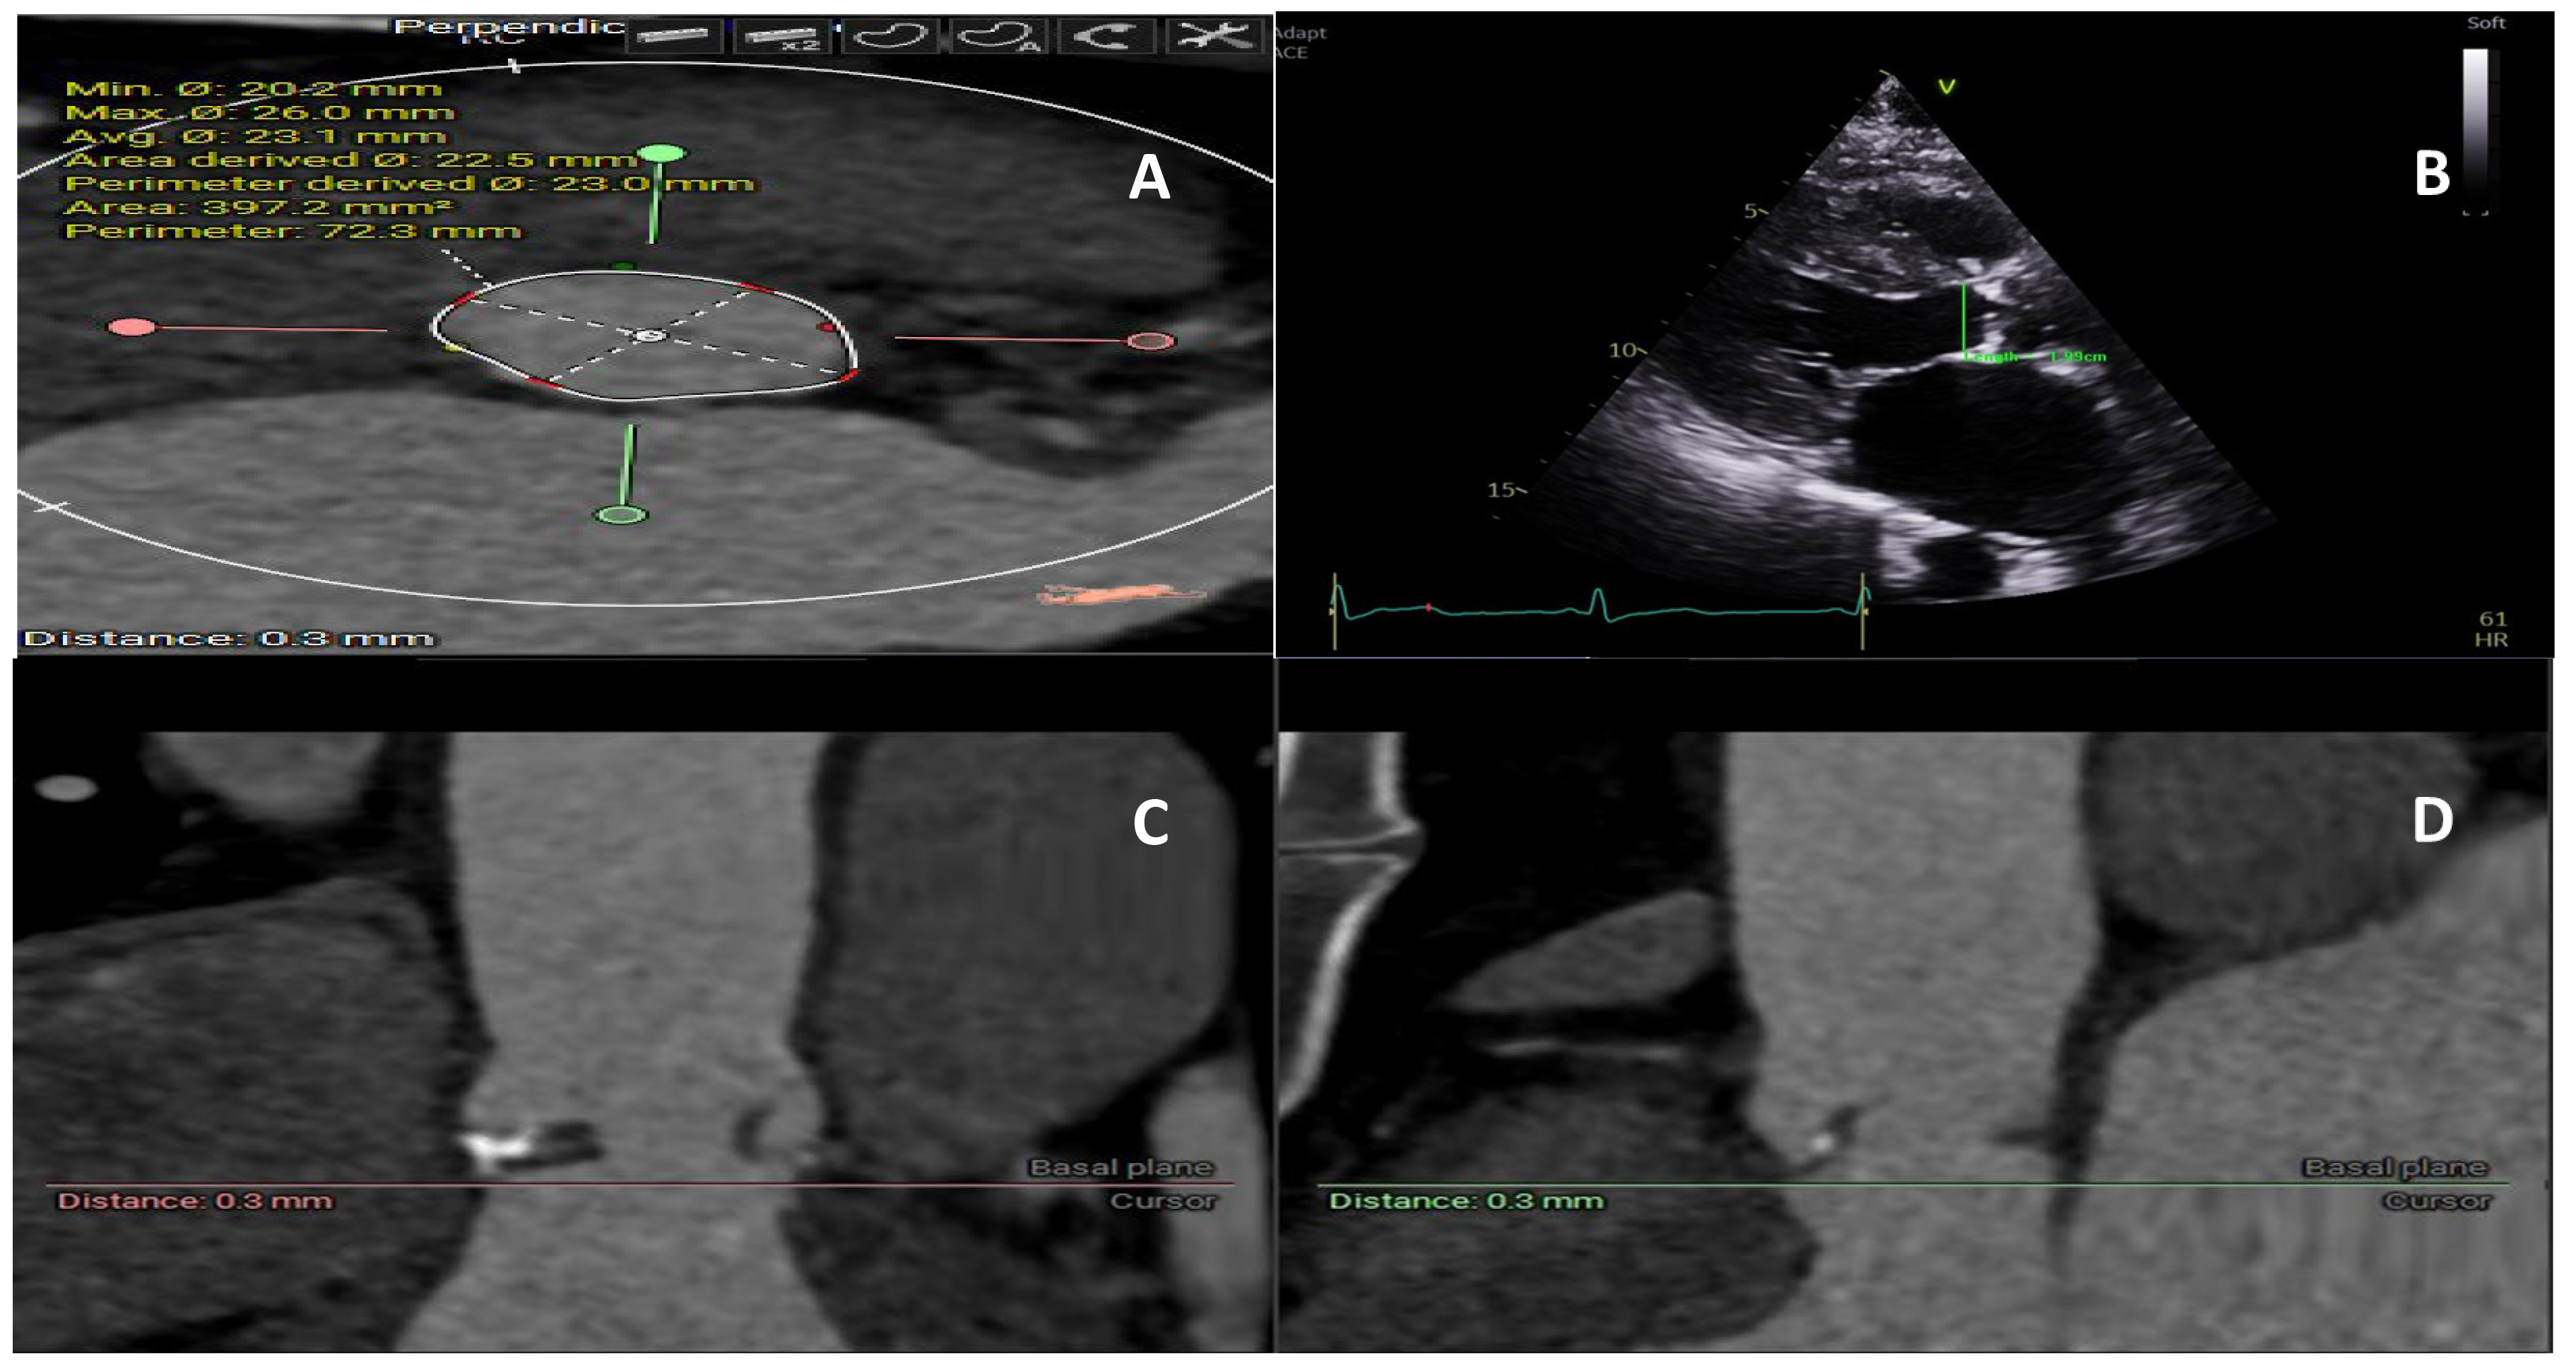

Despite recognizing the anatomical features of a small annulus more than five decades ago, there is currently no consensus on what defines a small annulus [5, 7]. These challenges stem from the discrepancy between the anatomical annulus used in surgical aortic valve replacement and imaging the annulus measured using echocardiography and computed tomography (CT). The junction, whereby the left ventricle meets the aortic root, represents the anatomical annulus and is used to attach the sewing ring of the surgical prosthesis. On the other hand, CT or echocardiography can be used to illustrate a virtual plane by connecting the lowest nadir of the aortic cusps. Historically, small aortic annulus was defined using echocardiography or direct sizing intraoperatively as less than 21–23 mm [7]. CT provides a three-dimensional structure of the aortic valve, and the aortic annulus area can be directly measured for valve sizing and procedural planning (Fig. 1). Subsequently, an area of less than 430 mm2 is being increasingly used to define small annulus in patients undergoing TAVI [11, 12]. For patients undergoing surgical aortic valve replacement (SAVR), CT is not routinely performed; however, recent data highlighted its potential role in improving valve sizing, reducing PPM, and decreasing interoperative variability [13].

Fig. 1. Aortic annulus measurement using computed tomography and echocardiogram. (A) Annulus size measurement on computed tomography providing area and perimeter. (B) Echocardiogram 2D measurement of the one axis of the annulus, (C) Computed tomography section provides a three-dimensional view of the annulus and its relationship to the surrounding structure. (D) Computed tomography section provides a three-dimensional view of the annulus and its relationship to the surrounding structure.

Limited cohort studies exist that assess the true prevalence of small aortic annulus. The Simvastatin and Ezetimibe in Aortic Stenosis (SEAS) study included 1560 patients with predominately moderate aortic stenosis and evaluated the prognostic role of small aortic annulus [14], finding a prevalence for small aortic annulus of 17%. Importantly, a small aortic annulus was defined using the inner diameter of the aortic sinotubular junction indexed for body height, but resulted in an average aortic annulus diameter of 21 mm. On the other hand, contemporary data reported a small annulus in 40% of patients who underwent SAVR [15, 16]. This percentage is slightly lower in TAVI cohorts, and a small annulus was reported in one-third of patients [3, 9, 12]. This difference could be attributed to the imaging modalities used in surgical versus transcatheter heart valve studies [17]. By measuring the smallest diameter of the small annulus, echo-based methodology is more likely to underestimate the aortic annulus, particularly those with an elliptical shape (Fig. 1) [17].